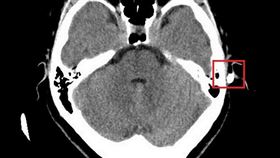

女跌倒護狗 頭撞餐桌筷子插耳、刺入頭皮

56歲的黃女士日前在家中走入客廳時不慎踩空,導致她重...